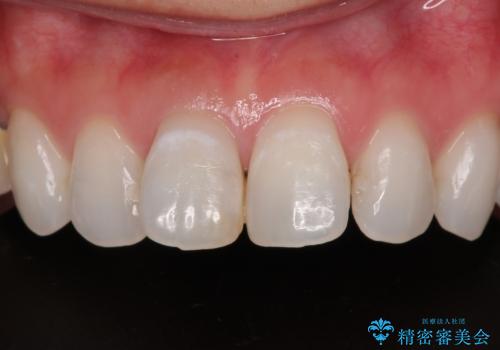

変色を綺麗にしたい 前歯と奥歯のオールセラミッククラウン治療

矯正治療で移動を終えた歯 オールセラミッククラウンでのむし歯治療